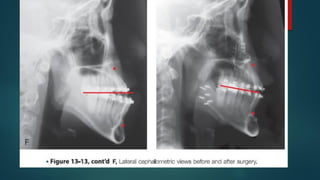

E, A frontal facial view confirms that the maxillary midline matches

face. F, Analysis of the facial profile and the lateral cephalometric

radiograph before surgery provides useful information about facial

height, incisor inclination, A-point to B-point relationship, maxillary

and mandibular projection, and chin morphology.